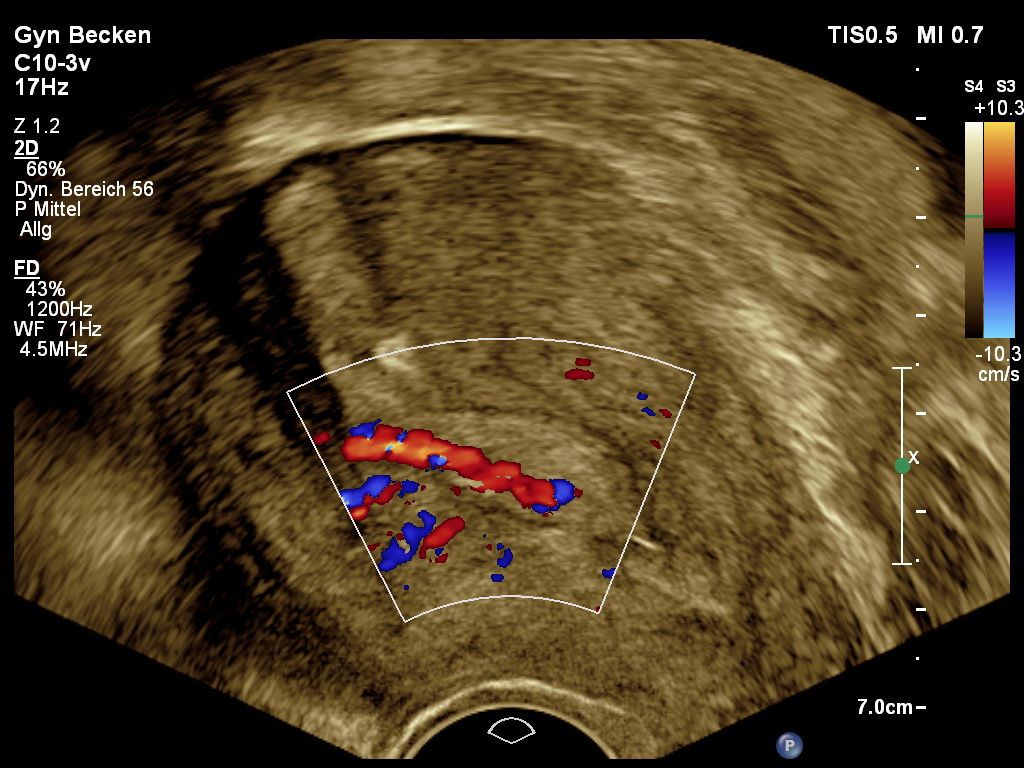

Unabhängig vom Ultraschall ist die Blutung nach den Wechseljahren ein frühes Verdachtsmoment für bösartige Veränderungen der Gebärmutterschleimhaut, welches weiterer, häufig operativer Diagnostik bedarf.  Der Ultraschall kann durch Messung der Dicke der Schleimhaut, durch Bestimmung der Durchblutung und Beurteilung der lokalen Struktur vorab zusätzliche Hinweise sammeln, die zu einer korrekten Erkennung bösartiger Veränderungen in über 91% der Fälle führen. Auch zur Ausbreitung der Veränderungen können wichtige Zusatzinformationen gesammelt werden. Insofern hat der Ultraschall einen festen Platz in der Diagnostik und Planung operativer Schritte bei solchen Veränderungen.

Endometriumpolyp-Doppler